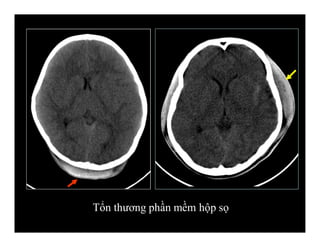

Tổn thương phần mềm

Tổn thương phần mềm hộp sọ

Tổn thương xương hộp sọ

Tổn thương phầnmềm hộp sọ